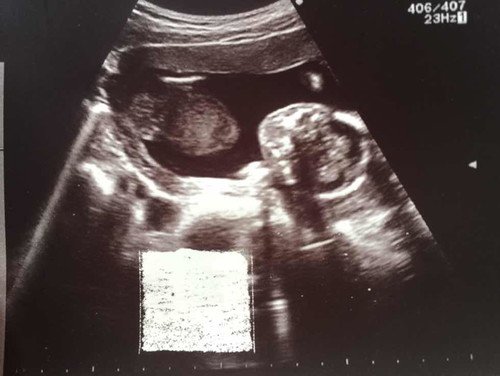

ไปอัลตราซาวด์ได้4เดือนพอดีวันนั้น หมอบอกเป็นผู้ชายไม่แน่ใจว่าจริงมั้ย ช่วยดูหน่อยค่า ตอนอัลตราซาวด์หัวน้องอยู่ฝั่งขวาของเรา

รูปนี้มองไม่เห็นเพศนะคะ

ไม่เห็นจ้า